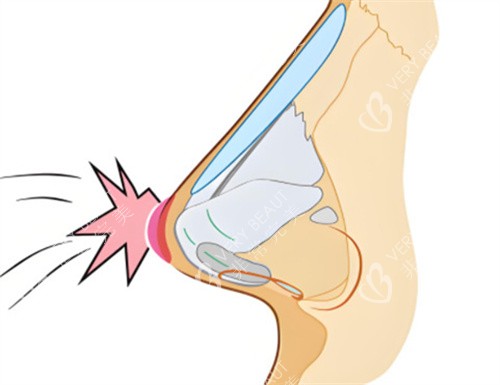

他用特色的知识给我分析了鼻子的情况,还提出了详细的修复方案。他的讲解让我对鼻修复有了更清晰的认识,也让我对他的特色能力有了信心。